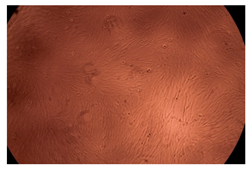

2.4. In Vitro Cytotoxicity Analysis

| Control |  |  | |

| Cop B | 10 µg/mL |  |  |

| 50 µg/mL |  |  | |

| 100 µg/mL |  |  | |

| Cop B/IMC = 10/1 (wt/wt) | 10 µg/mL |  |  |

| 50 µg/mL |  |  | |

| 100 µg/mL |  |  | |

| Cop B/Dorzolamide = 10/1 (wt/wt) | 10 µg/mL |  |  |

| 50 µg/mL |  |  | |

| 100 µg/mL |  |  | |